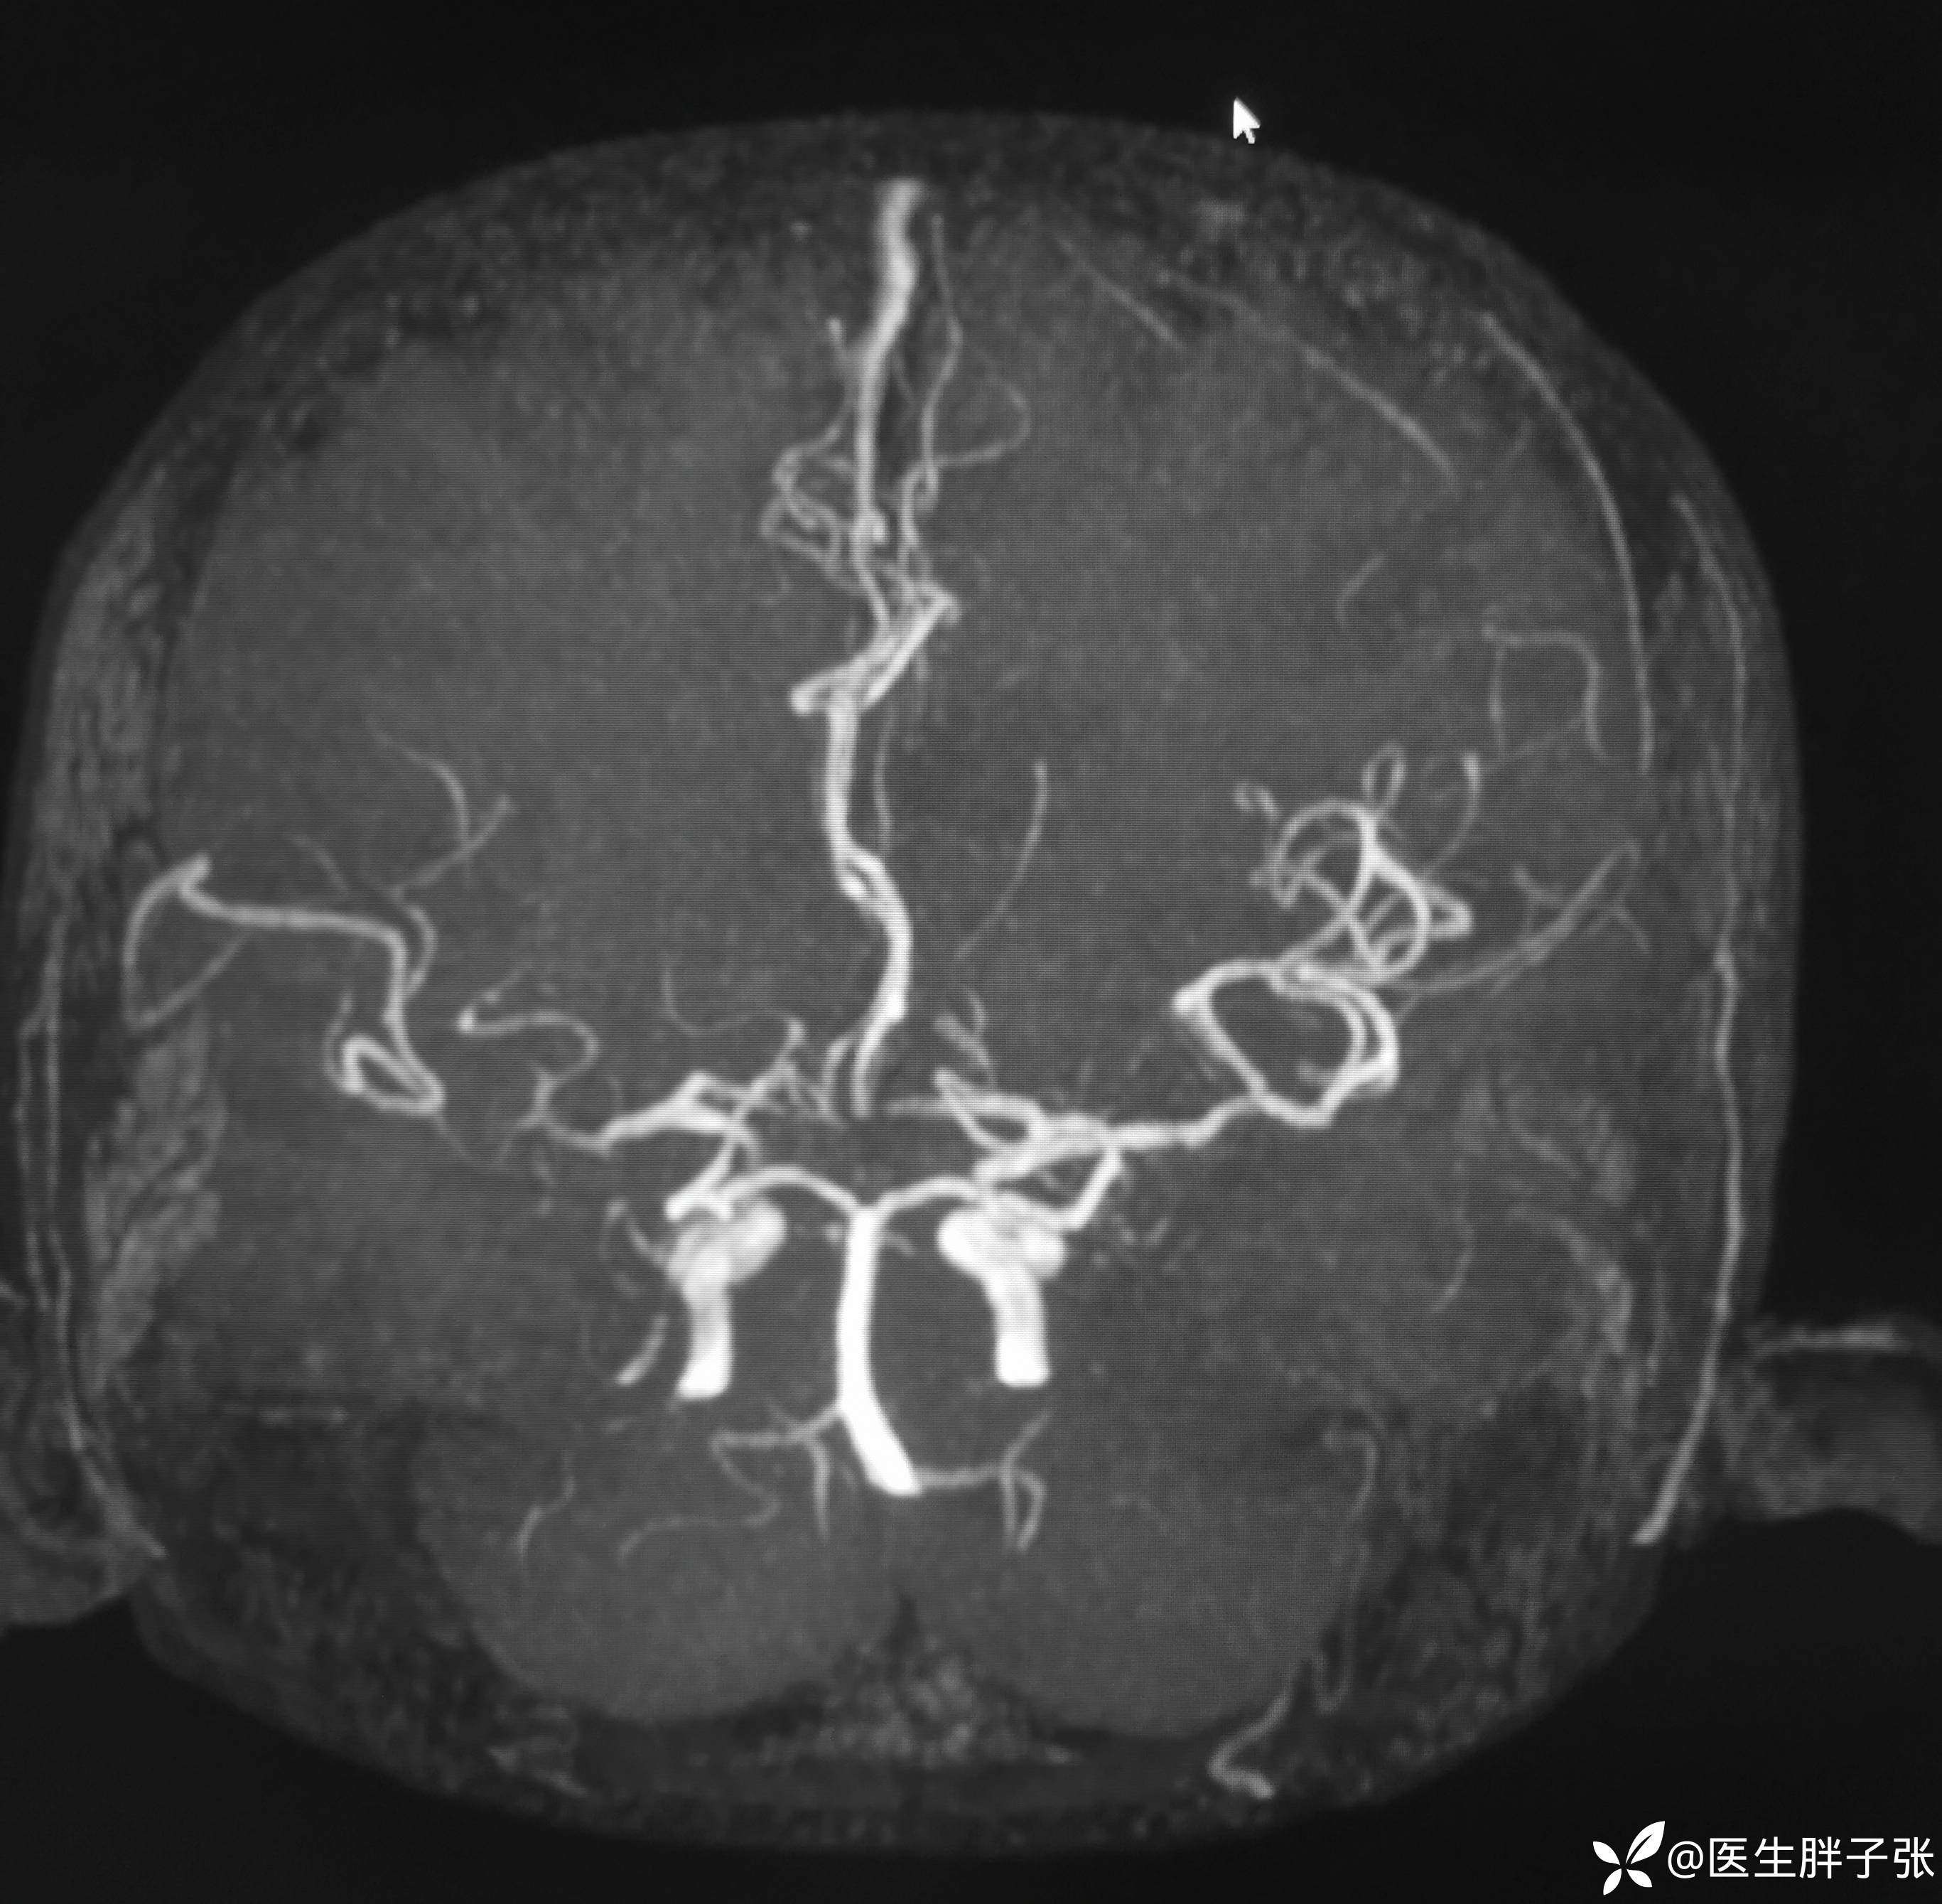

颅脑MR:右侧颞叶新近梗死灶;老年性脑改变;右侧大脑中动脉部分M2段及以远未见显示,建议头颈部CTA检查。

溶栓过程顺利,无并发症。患者发病前有腹泻,MRA提示右侧大脑中M2闭塞可能